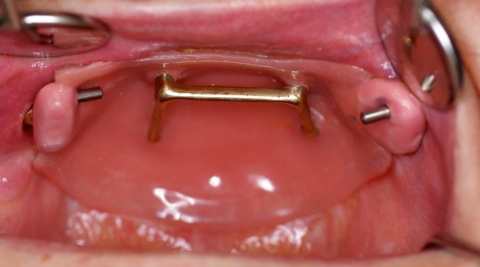

In den Ausführungen über die interdisziplinäre Zusammenarbeit der Zahnmedizin mit anderen Fachrichtungen in einem Bundeswehrkrankenhaus darf natürlich die seit vielen Jahren gewachsene und gelebte Zusammenarbeit mit der Abteilung für Mund-, Kiefer- und Gesichtschirurgie (Leiter: Prof. Dr. Dr. K.O. Henkel) im Bundeswehrkrankenhaus Hamburg nicht unerwähnt bleiben. Die Tatsache, dass beide Fachrichtungen die gleichen bzw. unmittelbar benachbarte anatomische Strukturen behandeln, führt zur einer engen Zusammenarbeit. Beispielhaft sei hier die Implantation enossaler Implantate zum Ersatz verloren gegangener Zähne erwähnt. Grundsätzlich können die Anforderungen des Zahnarztes und des Kieferchirurgen an die Implantation durchaus abweichen. Der Kieferchirurg wird überwiegend die Region zur Implantation favorisieren, die das beste Knochenangebot hinsichtlich der Höhe und Breite des Alveolarknochens bietet. Diese Position ist jedoch nicht unbedingt die beste Implantatposition im Hinblick auf die spätere Versorgung mit implantatgetragenem Zahnersatz. Zur Gewährleistung einer abgestimmten Therapie und einer auch für die prothetische Versorgung idealen Implantatstellung wurde bereits im Jahre 1993 eine gemeinsame Implantatsprechstunde eingeführt, in der sich jeweils ein Zahnarzt und ein ärztlicher Kollege der Abteilung für Mund-, Kiefer- und Gesichtschirurgie über Indikation und Machbarkeit der Insertion zahnärztlicher Implantate beraten und gegebenenfalls die entsprechende Antragstellung initiieren. Zur Vollständigkeit sei hier erwähnt, dass die Versorgung mit zahnärztlichen Implantaten grundsätzlich kein Bestandteil der uTV ist und immer der Genehmigung im Sinne einer Einzelfallentscheidung durch den Begutachtenden Zahnarzt der Bundeswehr im Kdo SanDstBw bedarf. Eine besondere Herausforderung stellt die kaufunktionelle und oral-ästhetische Rehabilitierung von Patienten mit schwierigen anatomischen Verhältnissen dar, so wie sie nach Verwundungen im Gesichtsbereich, aber auch nach Tumorerkrankungen in der Mundhöhle auftreten können. Auch hier hat sich die enge Zusammenarbeit der Abteilung für Mund-, Kiefer- und Gesichtschirurgie mit der Zahnmedizin bewährt (Abb. 5, 6, 7).